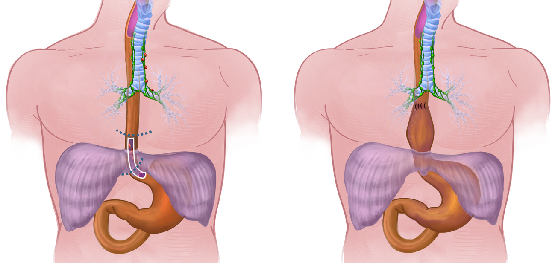

Detailreiche Fotografien aus der medizinischen Praxis ergänzen die Texte; moderne, genaue,

wissenschaftliche Zeichnungen geben Einblick in die Anatomie und die Funktion der Lunge und

anderer Organe.